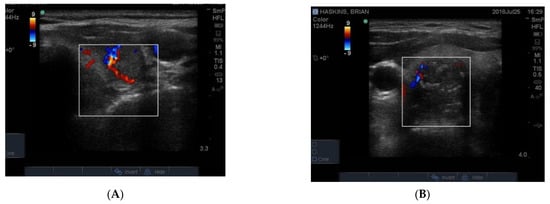

The blood supply to thyroid nodules is an important feature to be documented in the course of real time ultrasonography. There are three types of vascularity to be discussed. Firstly, the so-called hypoechoic halo surrounding a benign nodule is caused by compressed blood vessels which can be seen when the “colour” button is engaged. An example of this is seen in Figure 9A. Secondly, the degree of vascularity around the outside of a nodule is reflective of its activity and prominent blood supply around a nodule maybe a sign of thyroid cancer (Figure 9B) [] but can also be present around nodules shown by biopsy to be benign. It has recently been shown that blood vessels within a nodule, especially if it has other suspicious features (Figure 9B), may be a reliable sign of cancer [].

Figure 9.

Examples of vascularity around the edge of a benign nodule and (A) associated with blotchy macrocalcifications in a hard, irregular edged nodule that is suspicious for papillary cancer (B). Another example of macrocalcifications in papillary thyroid cancer.

In Figure 10 is shown matching images of a benign nodule without (A) and with (B) blood flow in the halo around the nodule.

Figure 10.

A small 8 mm benign nodule in the left thyroid lobe shown as an ultrasound image (A) and with surrounding vascularity in (B).